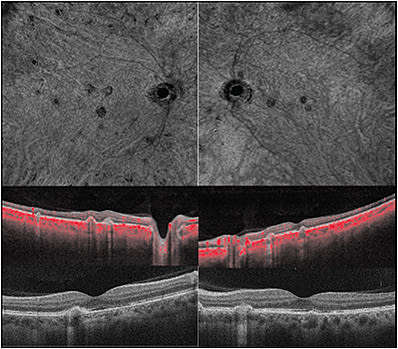

Finally, OCTA is useful in diagnosis and treatment of inflammatory choroidal neovascular membrane (CNVM). In contrast to the increase in flow seen in CNVM, inflammatory lesions demonstrate flow voids on OCTA. A 36-year-old female who presented as a second opinion regarding CNVM recalcitrant to multiple anti-VEGF injections demonstrated multifocal lesions with subretinal hyper-reflective material devoid of flow on OCTA (Figure 4). The lesions markedly decreased in size with the use of high-dose oral steroids.